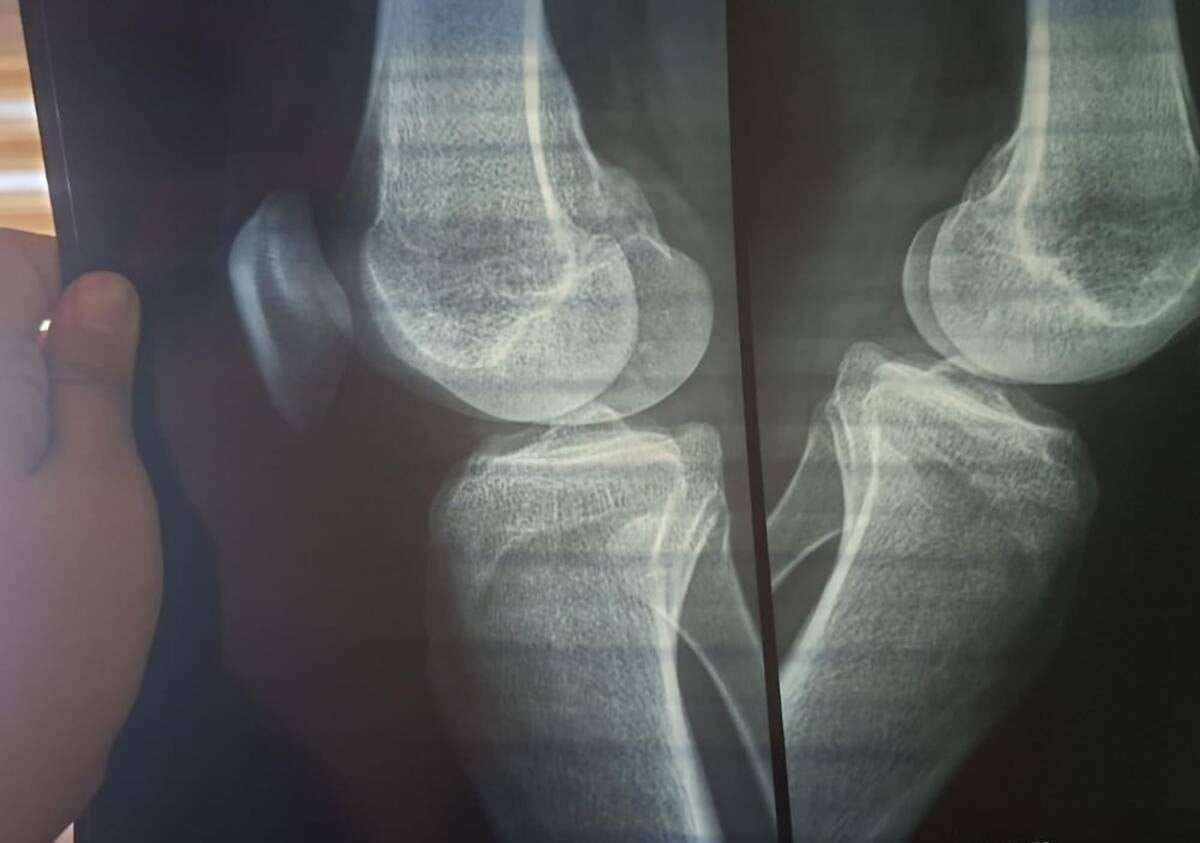

Señala que cuando llegó lo encontró con golpes que le ocasionaron una lesión severa cervical, golpes en la cabeza, mandíbula, rodillas, costillas y un hombro.

El menor fue trasladado por sus medios al Hospital General de León para su valoración, y los gastos tuvieron que correr por parte de su mamá, debido a que al no tener sangre en el banco del Hospital General, la ambulancia de Protección Civil no lo quiso trasladar.